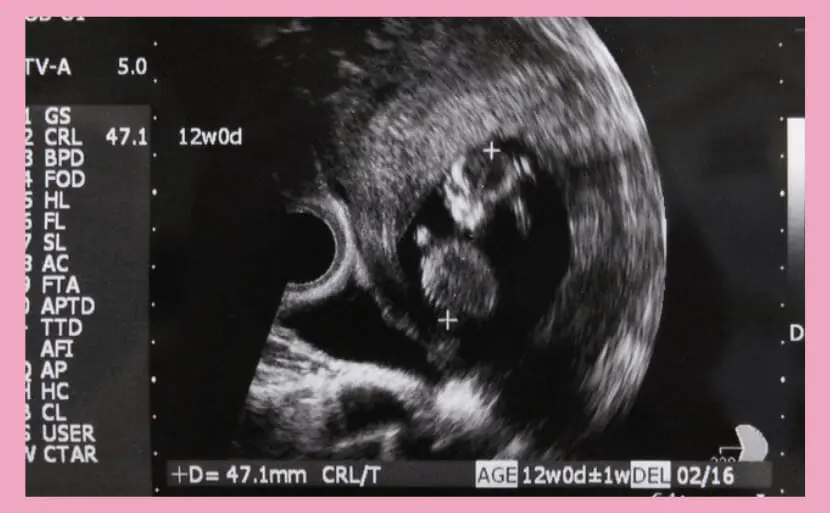

妊娠12週頃の赤ちゃんの平均的な大きさは、赤ちゃんの大きさを示す数値であるCRL(Crown-rump length)で、約5〜6cmです。

CRLとは、胎児の頭の先からお尻までの長さを測定したものになります。

エコーでわかるダウン症・12週目の特徴

ここからはエコー検査(超音波検査)でわかることに触れていきます。

エコー検査では赤ちゃんの成長の様子をみることができ、胎児の首のうしろや手足の長さなど部分的なところから染色体異常として知られる21トリソミー(ダウン症候群)の疑いを確認することができます。

いつから確認ができるかというと、一般的には10~15週目で21トリソミー(ダウン症候群)の疑いがあるかどうか確認されます。

首のうしろのむくみ

21トリソミー(ダウン症候群)の初期には後頭部、首の後ろにむくみがみられます。

検査結果の画像ではむくみの部分は暗く影のように映るのですが、21トリソミー(ダウン症候群)でない赤ちゃんの首の後ろと比べて厚く見える場合は21トリソミー(ダウン症候群)の疑いがあるといえます。

専門的な言葉では、首のうしろのむくみはNT(Nuchal Translucencyの略)という値で表されます。NTは妊娠11~13週目にみられるものであり、どの赤ちゃんにもあります。

NTの基準となる値は3.5mm未満ですが、CRL(crown-rump lengthの略)という頭からお尻までの胎児頭殿長と呼ばれる長さによっても判断が異なります。